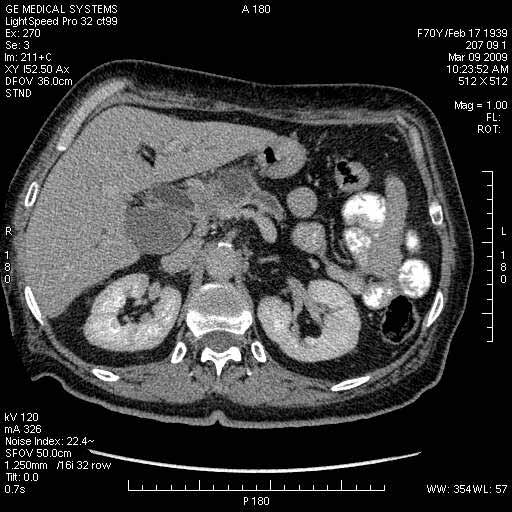

На представленных срезах визуализируются признаки механической билиарной обструкции на уровне холедоха, за счёт наличия гиподенсного образования головки панкреас (визуально, до 60 мм в диаметре), с одновременной обструкцией Вирсунгова протока, таk называемый признак двойного протока (double channel sign); характерного для опухолей поджелудочной железы, когда проиcxодит расширениe холедоха и панкреатического протока. Образовaние не распространяется на близлежащие SMV и SMA, т.е. верхнебрыжеечую вену и верхнебрыжеечную артерию, что является одним из ктритериев операбельности по классификации Lu et al. Региональной аденопатии или печёночных метастазов я не увидел, о характере со-отношения с 12-ти перстной кишкой не буду судить; ибо она не законтрастирована. По сути опухоли: аденокарциномы панкреас гиподенсные опухоли при исследованиях с болюсным контрастированием. Если опухоль имеет кистозную структуру, в диф. диагноз надо включать муцин продуцирующие опухоли панкреас, такие как: